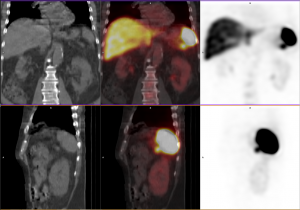

Scintigraphie à l’octreo-scan réalisée intialement dans l’hypothèse d’une TNE : fixation très faible du nodule de la queue du pancréas.

TDM et IRM : cinétique de réhaussement du nodule similaire à la rate.

Scintigraphie aux GR fragilisés : fixation des GR dans la lésion de la queue du pancréas confirmant son origine splénique.

Nodule de rate accessoire de la queue du pancréas.